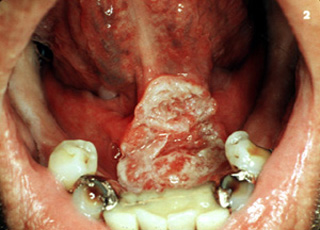

Carcinoma de verrugoso

Este tumor de crecimiento exofitico y de extensa

queratinización es el carcinoma verrugoso. Es infiltrante pero rara vez

da metastasis. Se caracteriza por una apariencia verrugosa con la producción de

una espesa queratina. A menudo tiene una apariencia clínica sucia, es sumamente bien diferenciado microscópicamente y puede ser equivocadamente

"subdiagnosticado" por el patólogo, como una reacción

proliferativa benigna. |